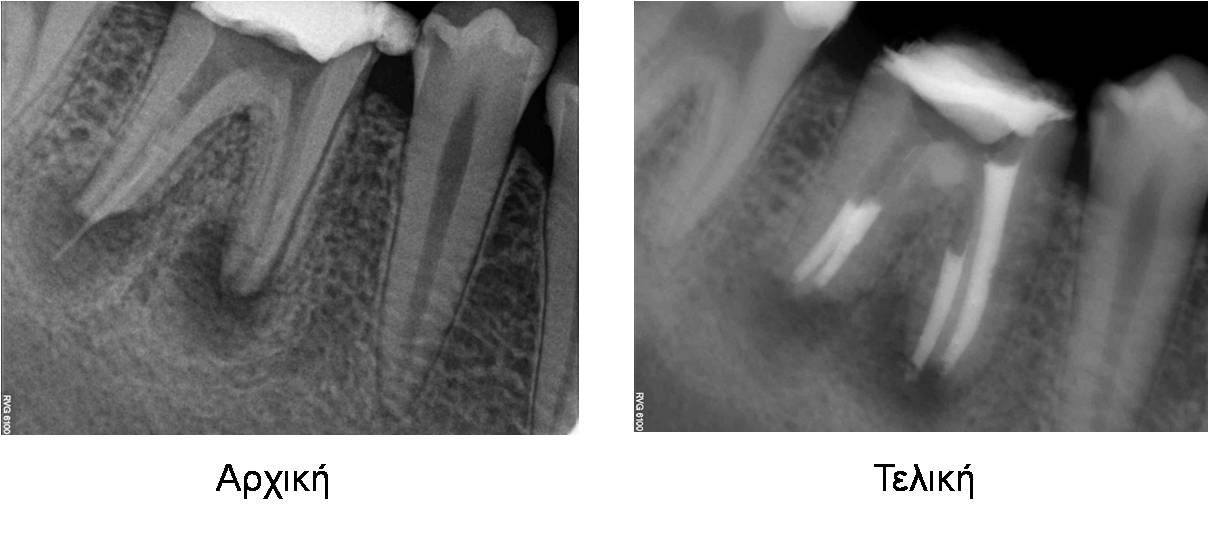

Περιστατικό 5

Αντιμετώπιση διάτρησης ρίζας

Περιστατικό 6

Περιστατικό 6

Ενδοδοντική θεραπεία σε δόντι με έντονη κάμψη ρίζας